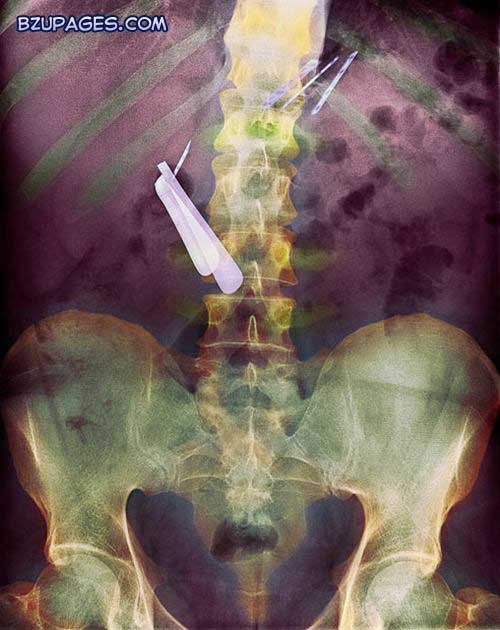

A coloured X-ray of the abdomen of a patient with dementia that has swallowed a razor (centre left) and razor blades (upper right)